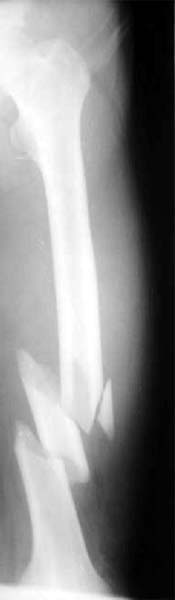

胫腓骨粉碎骨折 采用闭合穿钉法,带锁髓内钉内固定